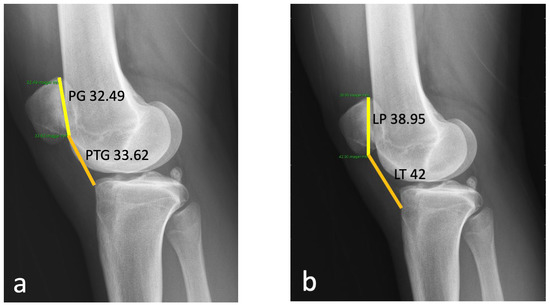

2.1. Case

3.2. Patella Alta

3.3. TT–TG Distance

3.4. Lateral Patella Tilt